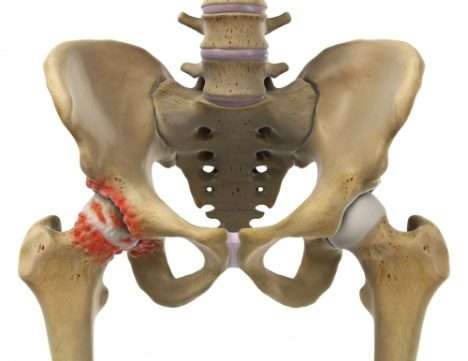

Hüftimpingement: Formstörung von Hüftkopf und Hüftgelenkspfanne

Als Hüftimpingement (femoroacetabuläres Impingement) bezeichnet man Bewegungsblockaden und Knorpelverletzungen, die aus der mangelnden Passung von Hüftgelenkspfanne und Hüftgelenkskopf herrühren.

Das Hüftimpingement ist eine subtilere Formstörung des Hüftgelenks. Auch diese Erkrankung kann Hüftarthrose auslösen.

Hüftimpingement bedeutet, dass das Hüftgelenk nicht in alle Richtungen frei beweglich ist. Aufgrund der Fehlform schlagen zwei Knochen aufeinander, was zu einer Überlastung von Gelenkknorpel und Weichteilen (Gelenklippe) führen kann.